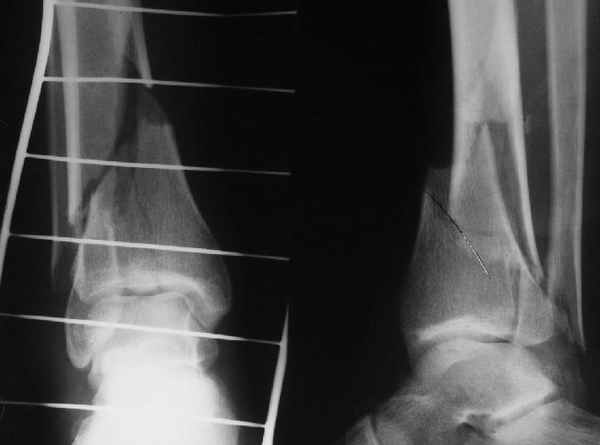

В приложении остеосинтез перелома шейки плеча LPHP у доктора из нашей клинике , через 8недель уже трудился в операционной

Кликните для загрузки файла 06.JPG

20KB (21241 bytes)

АМ> В приложении остеосинтез перелома шейки плеча LPHP у доктора из нашей

АМ> клинике, через 8недель уже трудился в операционной

Очень симпатично, спору нет, но полагаю, что и с Y-спицами полная реабилитация к этому сроку была бы вполне реальна.